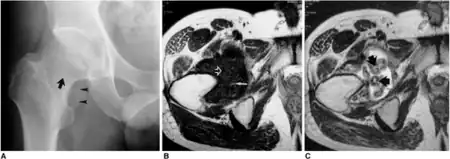

Radiography

Typical finding is of multiple, smooth, oval-shaped calcified masses within the joint space or bursa. They have a characteristic popcorn-ball appearance of calcified cartilage. With serial imaging, masses may be found to change in size, disappear, or migrate to recessed areas of the joint. They may pass from the main joint cavity into a neighboring synovial cyst. For this reason, a mass may not be appreciated within the actual joint space itself.

Additional radiographic findings include joint effusion and degenerative changes such as joint space narrowing, subchondral sclerosis, and osteophyte formation.

Magnetic resonance imaging

MR appearance depends on the composition of the intra-articular body. Entirely cartilaginous bodies will appear isointense to muscle on T1 and hyperintense to muscle on T2 weighted images. Partly calcified intra-articular bodies demonstrate foci of absent signal on all pulse sequences. Like CT arthrography, MR with gadolinium may be used to detect intra-articular bodies that have not yet calcified.